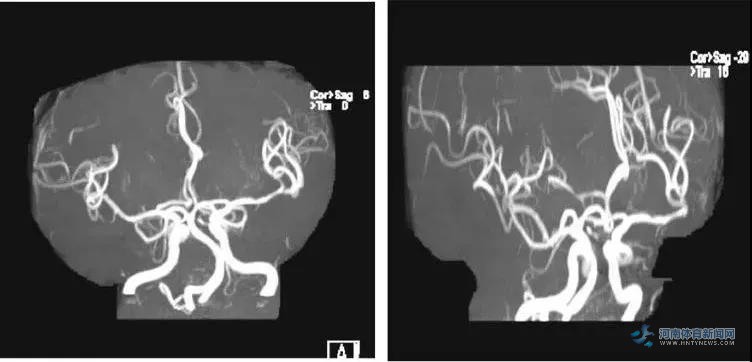

(3D复查MR)